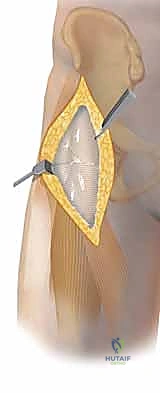

- النهج الأمامي (سميث بيترسون - Smith-Petersen Approach): يتم العمل في المسافة الفاصلة بين العضلة الموترة للفافة العريضة (Tensor Fasciae Latae) جانبياً والعضلة الخياطية (Sartorius) إنسياً. في العمق، يتم سحب العضلة المستقيمة الفخذية إنسياً. تقع العضلة الحرقفية المحفظية عميقاً ويجب إزاحتها لكشف محفظة المفصل. تعبر الأوعية الفخذية المنعطفة الوحشية الجزء البعيد من الجرح وتكون بمثابة علامة تشريحية. يقع العصب الفخذي إنسياً، وغالباً ما يُصادف العصب الجلدي الفخذي الوحشي سطحياً؛ ويجب حماية كلاهما بصرامة.

2. اختيار النهج الجراحي (Surgical Approach)

بناءً على الأشعة المقطعية ثلاثية الأبعاد، يحدد الدكتور هطيف مسار الدخول:

* إذا كان الكسر في الجزء الأمامي من رأس الفخذ، يستخدم النهج الأمامي (Smith-Petersen) لأنه يوفر رؤية ممتازة دون الإضرار بالإمداد الدموي الخلفي الحيوي.

* في الحالات المعقدة (Pipkin IV)، قد يستخدم تقنية الخلع الجراحي الآمن للورك (Ganz Surgical Dislocation)، وهي تقنية متقدمة جداً تتيح خلع المفصل جراحياً بشكل آمن تماماً، وإصلاح الكسر من جميع الجهات، ثم إعادته، وهي تقنية لا يتقنها سوى كبار جراحي العظام في العالم.